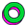

图1

(A)双侧颈总动脉数字减影血管造影(DSA),正位,显示双侧硬脑膜颈动脉海绵窦瘘(DCCF)Barrow D型(白箭头);

(B) 海绵窦(白箭头)和海绵间窦(黑箭头)的超选DSA;

(C) 右颈总动脉DSA,侧位,DCCF Barrow D型;

(D) 双侧颈总动脉DSA,正位,显示通过弹簧圈和Onyx(Medtronic)(白色箭头)铸型DCCF完全闭塞;

(E,F) X-rays 显示双侧DCCF栓塞后弹簧圈和Onyx(Medtronic)最终铸型,(E) 正位和(F) 侧位。